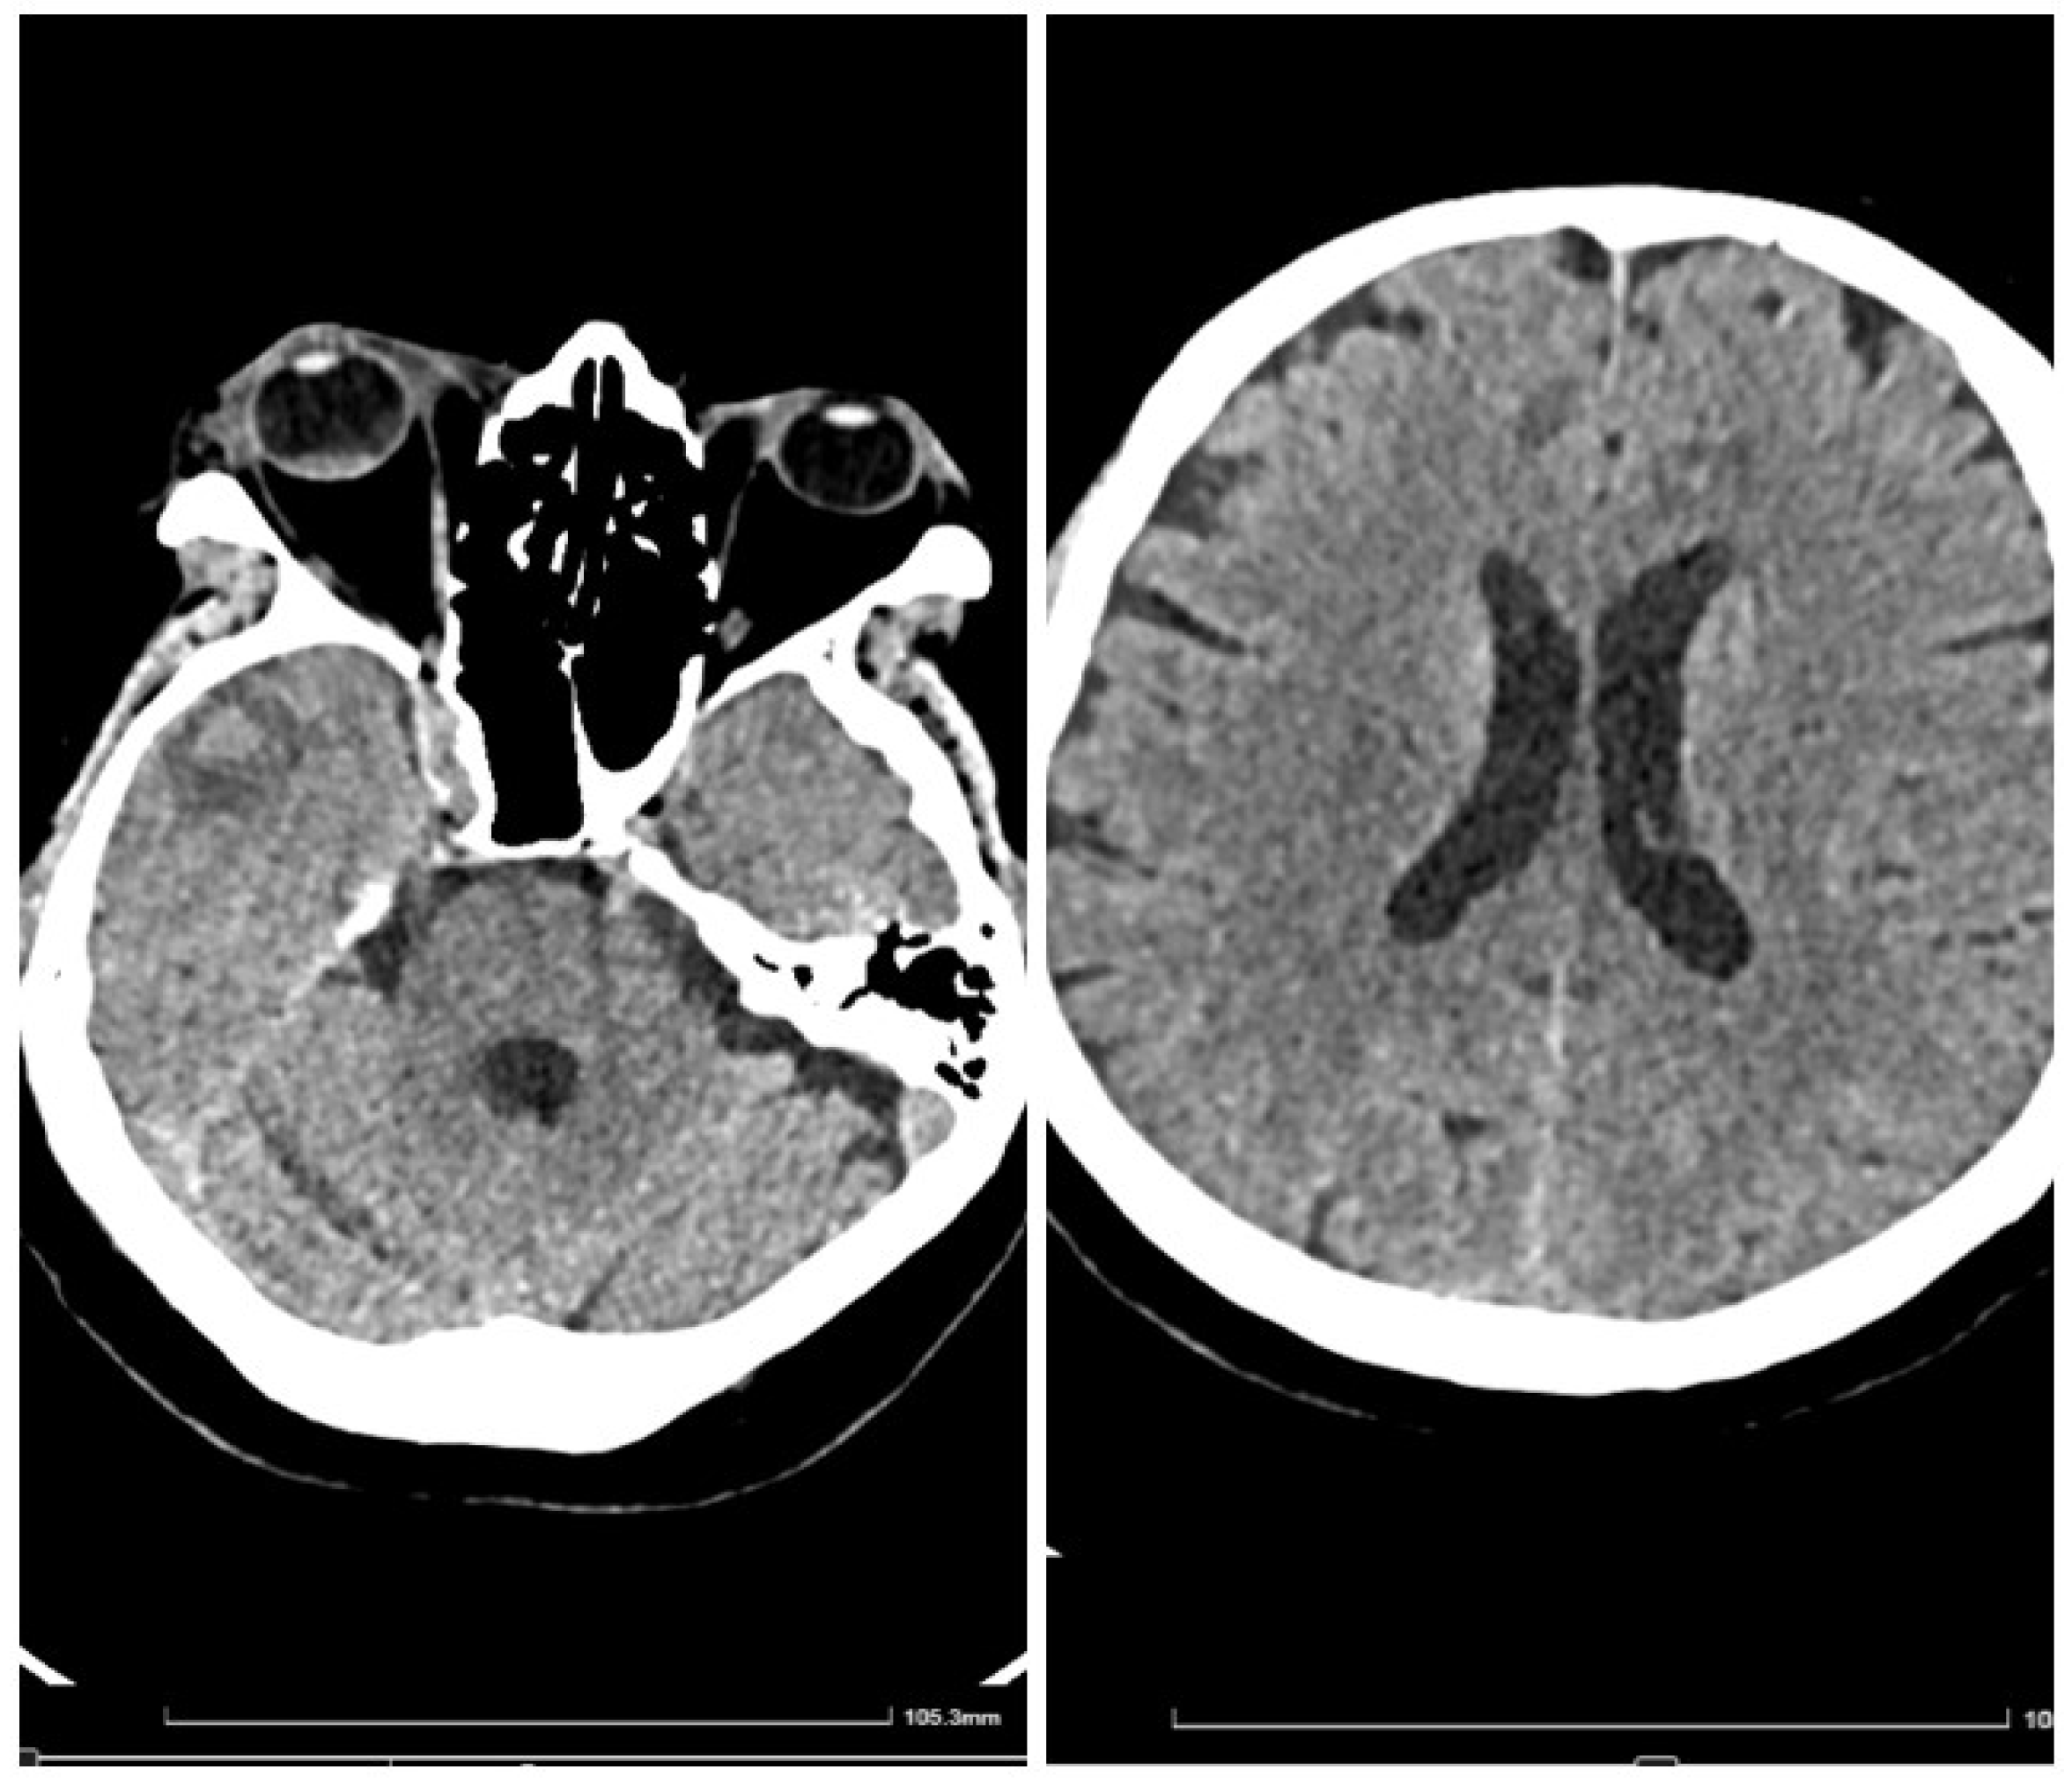

In early May 2023, the patient developed a respiratory illness that was treated with iv. gentamycin and ceftriaxone for 7 days in a territorial hospital and discharged. In late May 2023 he developed right retrorbital pain, painful right red eye with acute vision loss, headaches, 7 kg weight loss, and aggravated fatigue that were not controlled with usual medication and cough. The patient was admitted to the Internal Medicine Department for further evaluation. We performed a native cranial CT (Figure 1) and an MRI without contrast which showed multiple lesions -10- that were classified as undetermined lesions on CT scan and possible abscessed metastases on the MRI.

Figure 1. Initial cranial CT (no contrast).